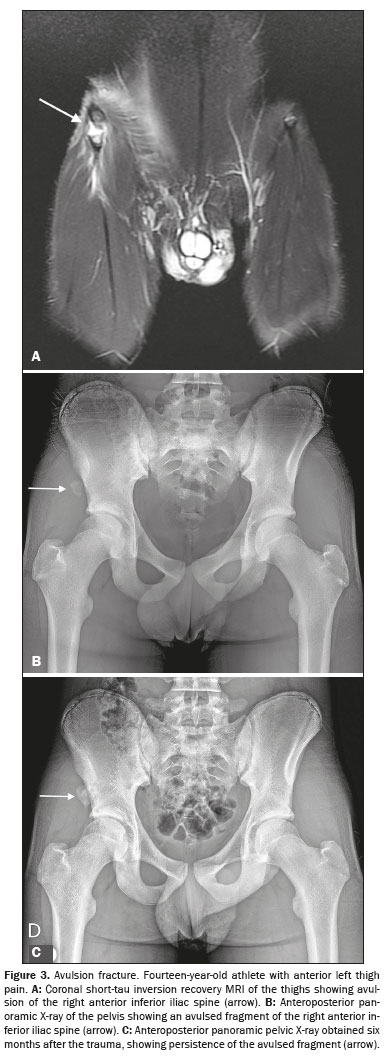

The study sample comprised 33 male athletes who underwent MRI scans. The mean age of the participants was 13.1 ± 1.7 years. Suspected injuries to the right lower limb were reported in 17 athletes (51.5%). The most commonly affected apophyses, in descending order, were the anterior inferior iliac spine, in 14 cases (42.4%), the ischial tuberosity, in 12 (36.4%), the iliac crest, in three (9.1%), the anterior superior iliac spine, in three (9.1%), and the lesser trochanter of the femur, in one (3.0%). Figures 1, 2, and 3 show exemplary images of the injuries.

The MRI scans revealed avulsion injuries in 21 athletes (63.6%) and apophysitis in 11 (33.3%). Only one athlete (3.0%) had normal MRI findings. The MRI findings for the cases of avulsion fracture included apophyseal displacement in all 21 cases (100%), periphyseal edema in 20 cases (95.2%) (Figures 1A and 3A), bone marrow edema in six cases (28.6%), and intermuscular fluid collections in 14 cases (66.7%) (Figure 1B). In cases of apophysitis, periphyseal edema was observed in five cases (45.5%). As illustrated in Figure 2, bone marrow edema was noted in all 11 cases of apophysitis (100%). Intermuscular fluid collections were identified in only two (9.5%) of the 21 athletes with avulsion fractures.

A total of 25 athletes underwent X-ray, which identifying avulsion fracture, as depicted in Figures 1D, 3B, and 3C, in 11 cases (44.0%). The median displacement observed on X-ray was 4.7 mm (range, 2.5–7.5 mm).